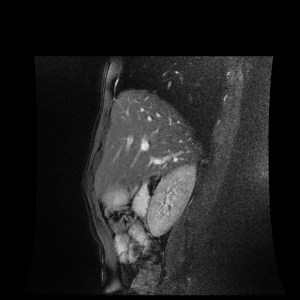

test_MR_NO_20180123_014